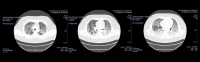

Coinfection with SARS-CoV-2 and Influenza A Virus in a 32-Year-Old Man

BACKGROUND There was a growing presumption that coinfection with severe acute respiratory syndrome coronavirus 2 (SARS-CoV-2) and another viral respiratory illness was nonexistent. Although there has been an increasing number of coinfection cases since the beginning of the SARS-CoV-2 pandemic, there is still a significant lack of information regarding the symptomatology, treatment, prognosis, and reasoning behind coinfection. This raises concern of the possibility of misdiagnosis or delay in treatment. CASE REPORT This case report discusses a coinfection of SARS-CoV-2 and Influenza A in a 32-year-old man to highlight that these viruses can coexist within the same patient. This patient unfortunately died of persistent respiratory failure after several days in the ICU. CONCLUSIONS Coinfection of SARS-CoV-2 and Influenza A can occur and lead to a poor prognosis.